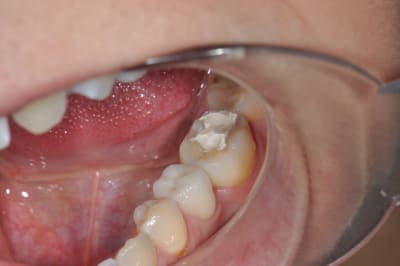

sur cette dent vous faites bio + inlay

ou alors, qui fait une CCC ?

Ce qui m'interpelle c'est que j'ai l'impression qu'on voit la dentine sur la face occlusale, est-ce que toutes les dents sont comme ça ?

37 semble aussi abrasée, donc je soupconne une abrasion et des parafonctions

couronne CAO

Je tenterais l'onlay . (+endo)

Si t'arrives à faire ton endo sans élargir plus la chambre, c'est une indication d'Inlay.

Mais il y a fort à parier au regard de la courbure importante de la racine mésiale qu'il faudra élargir cette chambre en mésiale, à ceci s'ajoute une carie débutante toujours en mésiale (sans parler des caries multiples un peu partout), donc on se dirige à mon avis vers de la prothèse périphérique.

Par contre le titre dit "bio et ensuite", ben ensuite, c'est soins conservateur multiples (y a du boulot), motivation hygiène (c'est bizarre toutes ces caries dans une bouche présentant un implant, signe de patient généralement motivé!), et enfin CCC.

la limite distale finira en juxta osseux.non?

on peux quand meme faire un inlay?

Je privilégierai l'inlay sauf si ça le fait pas une fois la carie nettoyée.

Il y a de bonnes parois dentaires, ça me ferait mal au coeur de les supprimer.

L'émail perdu complique un peu l'inlay-onlay.

1er choix inlay-onlay, 2e choix ccc, pas de tenon métal ou de IC.

Ceux qui font un "inlay", pourquoi pas plutôt un composite direct ?

Question pour ceux qui en ont fait plusieurs avec un peu de recul, dans le cas présenté, hormis la sous-occlusion, ça reste de l'inlay ou vous recouvrez la face occlusale ?